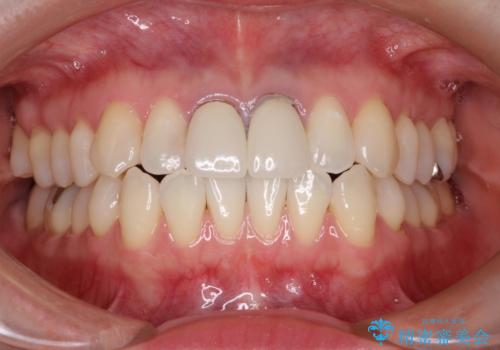

前歯の根元が黒い オールセラミッククラウンの装着による改善

かぶせ物と歯の境目の再設定を行い、適合の良いかぶせ物を装着することで、審美的に自然な状態に改善することができました。